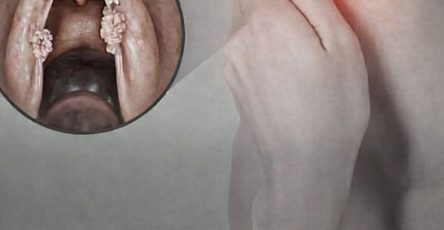

Des plaques rouges, vives et douloureuses sont apparues sur son visage et son cou.

Cette réaction cutanée soudaine et la fièvre ont nécessité une consultation urgente chez un dermatologue.